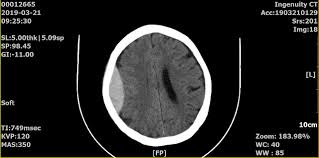

뇌출혈 수술은 뇌혈관이 파열돼 뇌 안에 피가 고인 상태를 제거하거나 압박을 완화하는 수술로, 이후 **의식회복 여부는 환자 예후를 결정하는 핵심 요소**입니다. 회복은 개인의 상태, 출혈 부위와 범위, 나이, 기저질환 등에 따라 크게 차이가 있으며, 적절한 치료와 재활, 가족의 지지가 매우 중요합니다.

- 뇌출혈 후 의식저하는 뇌압 상승, 뇌 손상, 뇌부종 등으로 발생합니다.

- 출혈의 크기와 위치: 뇌간·기저핵 출혈은 의식회복 가능성이 낮음